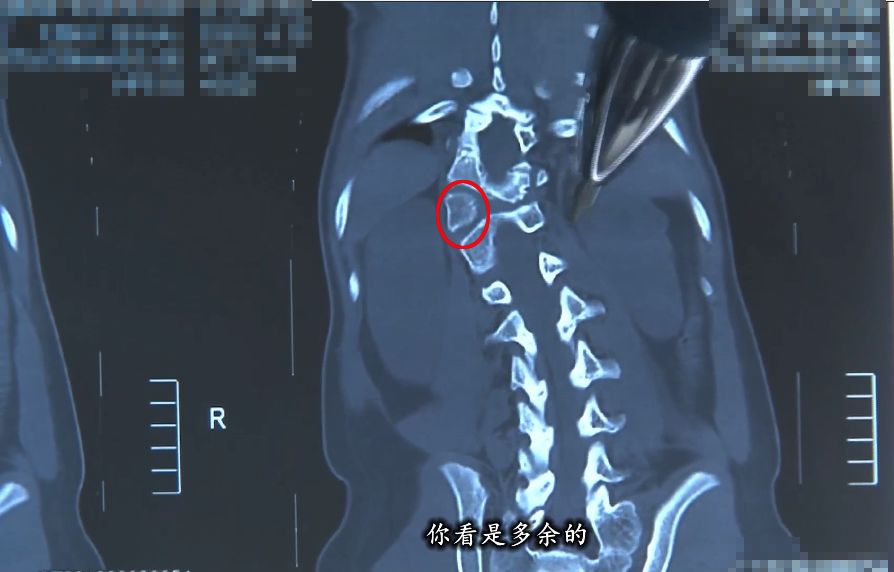

脊柱側彎,即脊柱向側方彎曲——正常人的脊柱從正面看是直的,而脊柱側彎患者的脊柱從正面看是呈字母「C」形或者「S」形的。

由于人體的脊柱是三維結構,從三維上看,脊柱側彎會伴有脊柱結構的旋轉,是一種三維的脊柱畸形。

半椎體切除術,是目前治療半椎體畸形最理想的方法。